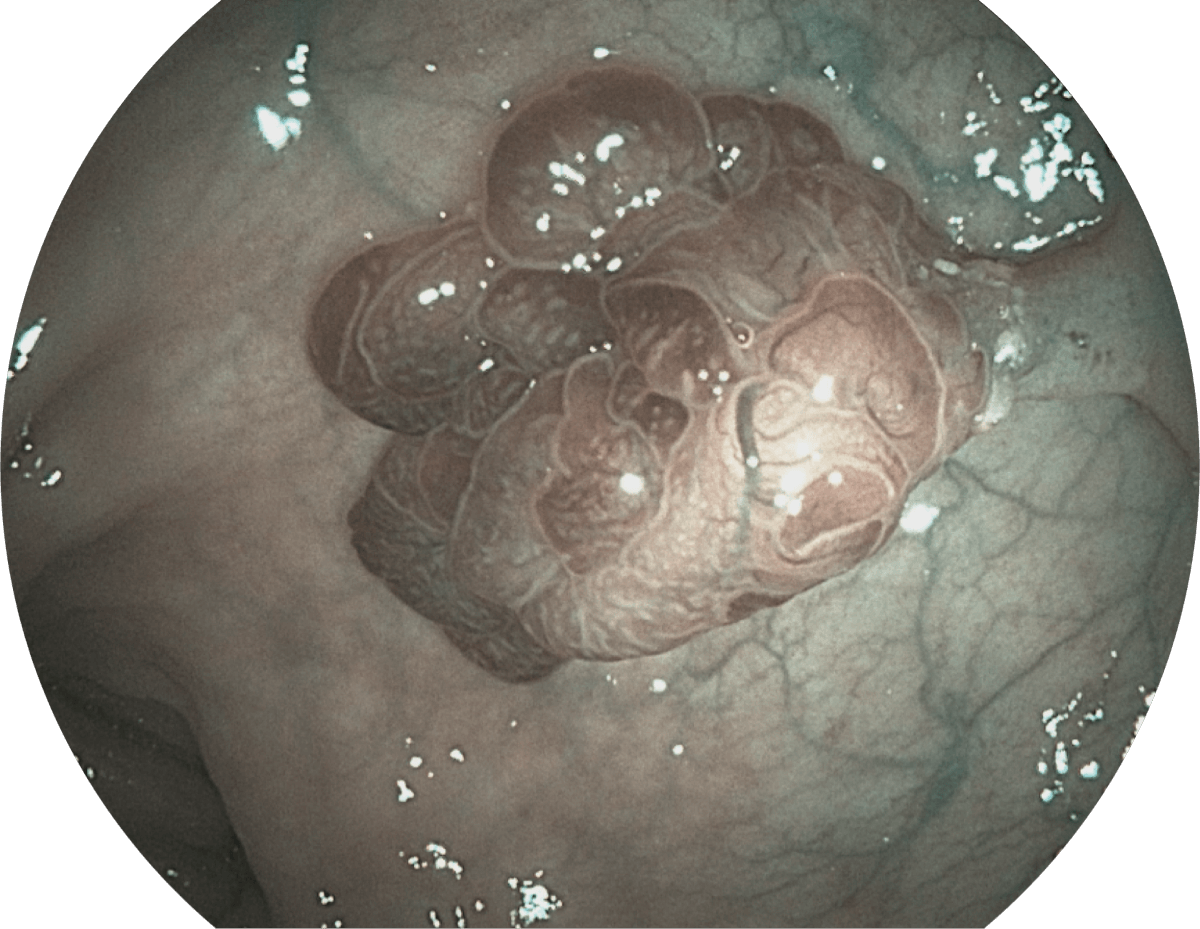

具有聚谱成像技术(SFI)及光电复合染色成像技术(VIST),可完美呈现粘膜细节及病变特征。

( Versatile Intelligent Staining Technology, VIST )

VIST